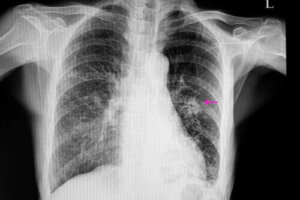

I slike tilfeller vil en lungeknute ha et uregelmessig utseende med dårlig definerte kanter; dette er synlig på røntgenbildet. Dessuten er de vanligvis mindre enn de godartede. I tillegg er de en del av visse risikofaktorer, for eksempel:

Når dette er gjort må en lege utføre visse avbildningstester for å lokalisere knutepunktet. I tillegg vil bildene vise visse egenskaper som form og størrelse. Dette er fordi de er viktige for å skille en godartet knute fra en muligens ondartet variant.

De vanligste måtene å diagnostisere dem på, er via røntgenbilder av brystet og computertomografier. For å finne den eksakte årsaken til en lungeknute gjør også legene noen ganger biopsier, da disse lar dem analysere vevet.